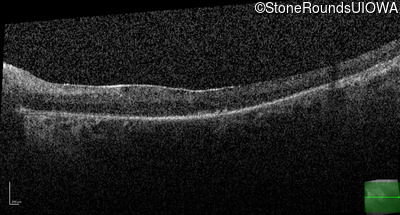

Age at visit: 59 years